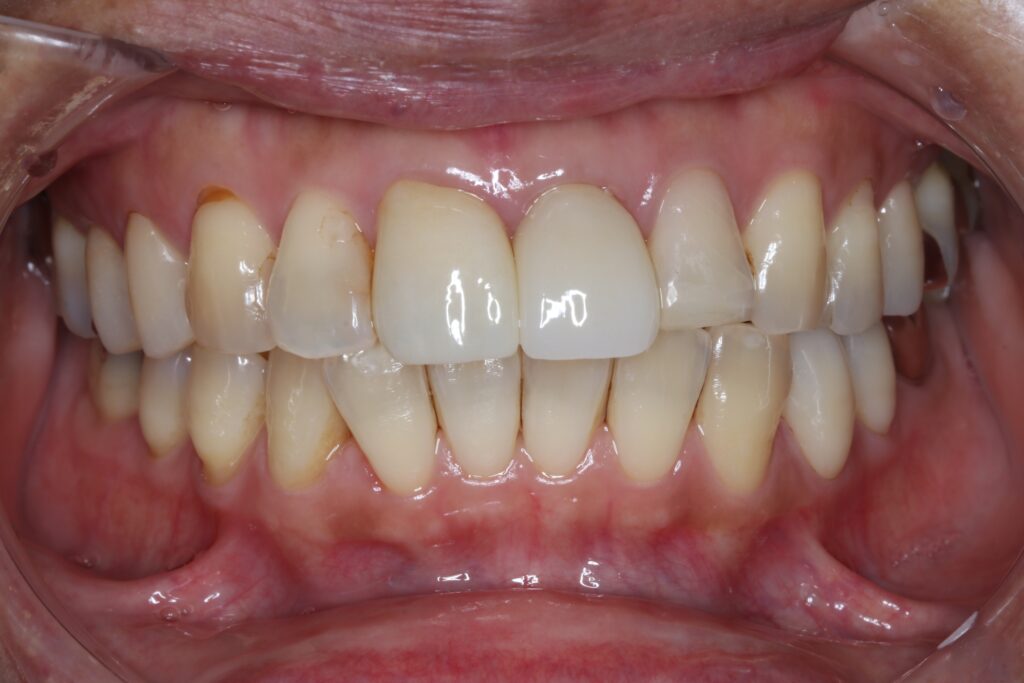

セラミック症例①

年齢40代女性

治療期間1ヶ月

治療内容ジルコニア、セラミックインレー、セラミッククラウン

治療箇所左上1番、2番 左下5番、7番 右上1番、2番、3番、4番、5番 右下5番、6番、7番

治療費用100,000円